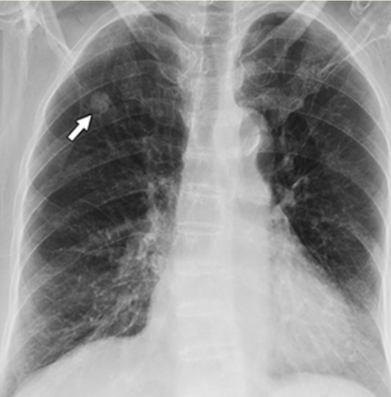

Renal Cell Carcinoma with Lung Metastasis in Association with Scleroderma

Attapon Cheepsattayakorn, Ruangrong Cheepsattayakorn and Porntep Siriwanarangsun. 5(12): 01-05.